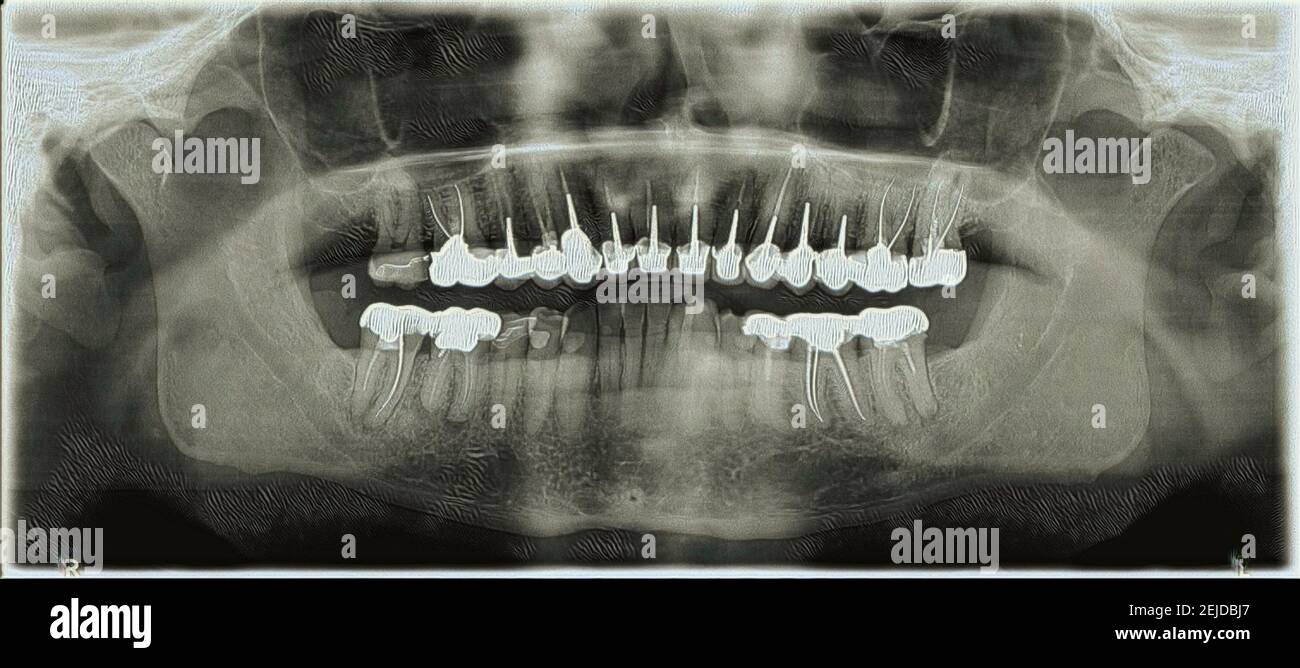

From www.alamy.com

Dental XRay panoramic of upper and lower jaw Stock Photo Alamy What Can A Jaw X Ray Show This is useful, as your dentist can recommend certain treatments (for example, braces, implants, or wisdom teeth removal) based on your results. P athologic conditions affecting the jaw are common yet not frequently imaged or encountered by radiologists. Jaw tumors and cysts — sometimes referred to as odontogenic or nonodontogenic, depending on their origin — can vary greatly in. So,. What Can A Jaw X Ray Show.